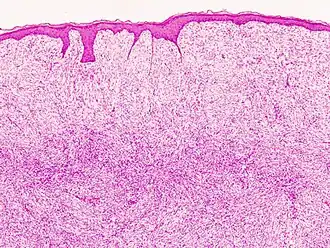

| Histopatologia de uma recorrência em H&E | |